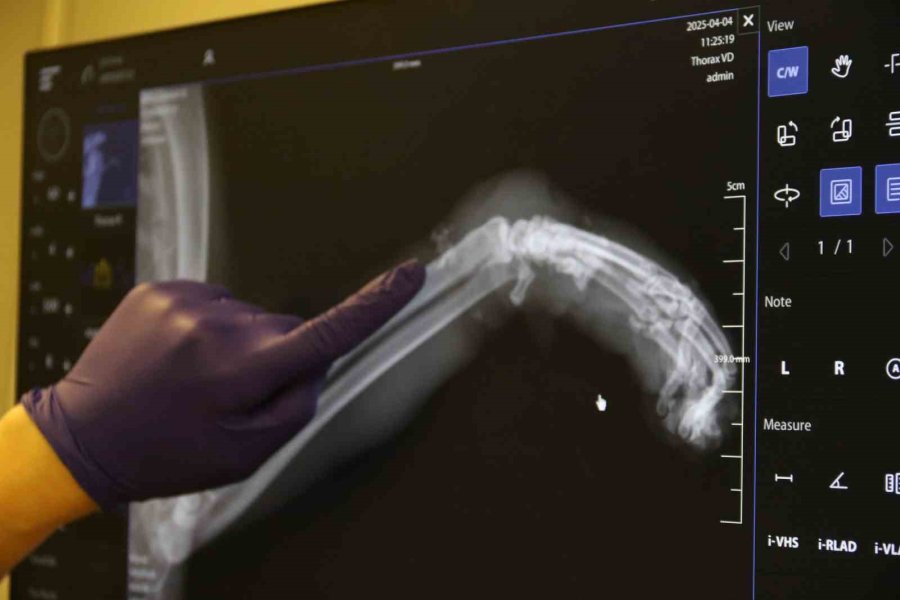

Geçtiğimiz günlerde Odunpazarı Emek Mahallesi'nde kimliği belirsiz kişi veya kişilerce bir kedinin sol ön bacağına paket lastiği takıldı. Kedinin patisine birkaç kez sıkı bir şekilde dolanan paket lastiğin talihsiz hayvanın ayağının şişmesine neden oldu. Bunu fark eden bir hayvansever kediyi Kurtuluş Mahallesi'ne bulunan bir veteriner kliniğine götürdü. Burada tedavi altına alınan hayvanın öncelikle patisindeki lastik çıkarıldı. Sol ön ayağında ödem biriken kedinin patisinin röntgeni çekildi. Antibiyotik tedavisi uygulanan kedinin ayağının kangren olma riski ve buna bağlı olarak ayağının ampute edilme ihtimali var. Tedavi altına alınan kedi gözlem altında tutuluyor.

Kedinin tedavi süreci hakkında bilgi veren Veteriner Hekim İlayda Ulus, "Kedi saat 4 gibi geldi kedimiz. Bacağı aşırı derecede şişmiş, ödenmiş şekilde geldi. Biz ilk başta kırık sandık. Ama muayene ettiğimizde 4-5 kere bağlanacak şekilde lastiğin burasını boğmuş olduğunu gördük. Bu bilinçli şekilde yapılmış. Dolaşım bozmak adına. Kimin yaptığını bilmiyoruz. Hasta sahibimiz getirdi çok üzülerek. Biz de tedaviye başladık şu anlık. Sokak kedisi, birisi sadece dükkanında bakıyormuş, gidip geliyormuş. Bir haftadır yokmuş kedisi. Aramışlar, birisi haber vermiş tasmasından bularak o şekilde geldi. Oradaki tüyleri özellikle tıraş ettik. Ölü dokuları aldık. Baya bir kan toplamış ve ölü dokular birikmiş. Onları temizledik, tıraş ettik. Antibiyotik tedavisine başladık. Şu anda sabah akşam olacak şekilde krem sürüyoruz. Yarın tedavisi yapıyoruz. Oradaki kan akımını hızlandıracak kremler, özellikle fizik tedaviler uyguluyoruz. Şu anda 3-4 gün takip edeceğiz. Eğer iyileşme görmezsek amputeye doğru gidebiliriz. Şu anda sol ön ayağını kaybetme ihtimali var. Birkaç kere böyle tasma boğulmuş şekilde geldi, boyundan yara almış kediler. Başka tekme çok geldi, göğüs kırıkları. Bu tür vakaları gördük. Onların ağzı var, dili yok. Bizden daha daha masumlar. Bu şekilde olması bizi çok üzüyor, derinden üzüyor. Hayvan sevmeyen, insan sevemez. Bu şekilde çok daha duyarlı ve dikkatli olmalarını bekliyoruz" dedi.